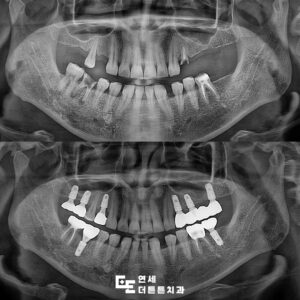

주기적인 경과 관찰 결과,

잇몸 상태와 교합이 양호하게

유지됨을 확인하였습니다.

환자분의 청각 인지 장애로 인해

초기 의사소통에 어려움이 있었으나

이후에도 정기적인 검진을 통해

지속적인 관리를 진행 중입니다.